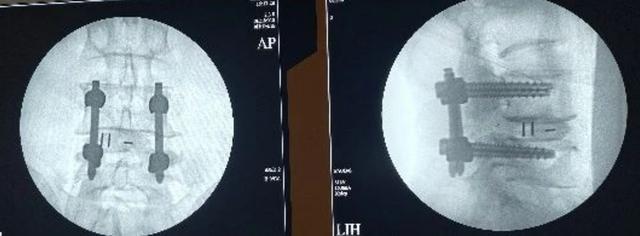

▲术后即刻透视见滑脱的椎体已复位